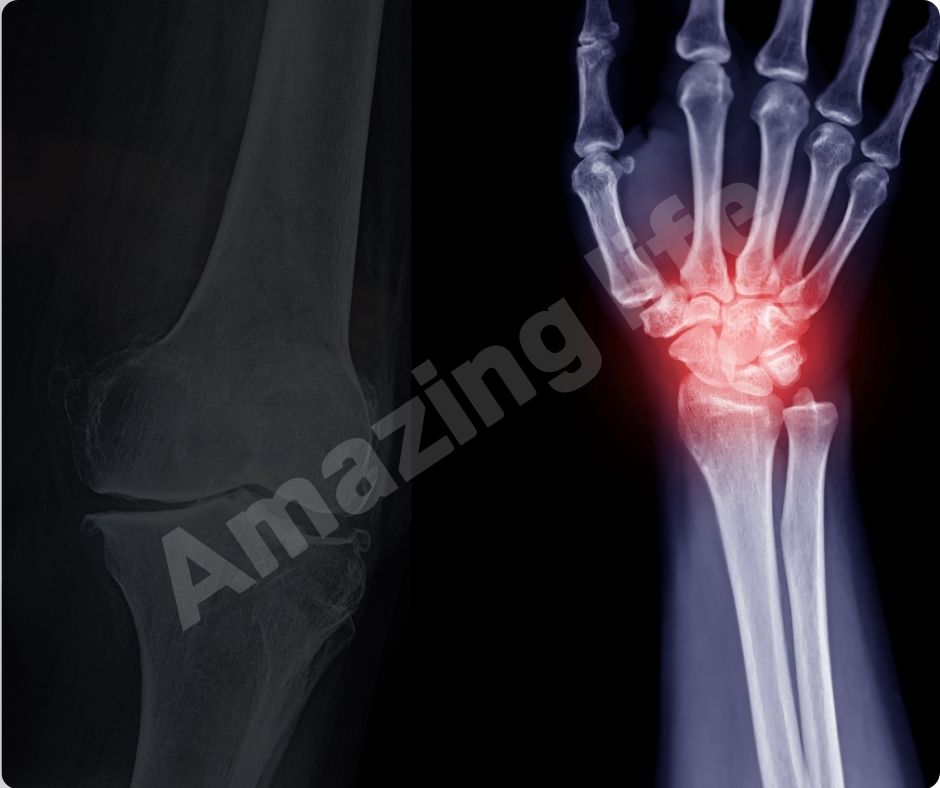

관절 통증 완화

많은 연구에서 글루코사민의 효능이 관절 통증을 완화하는 데 효과적이라는 결과가 나왔습니다. 최근 연구에 따르면, 글루코사민과 콘드로이틴 보충제를 꾸준히 섭취하면 심혈관 질환 사망률이 65%까지 감소할 수 있습니다.

염증 감소

글루코사민의 효능은 염증을 감소시키는 데도 효과적입니다. 관절염은 염증으로 인해 발생하는 경우가 많으므로, 글루코사민을 통해 염증을 줄이면 관절염 증상을 완화할 수 있습니다. 이는 자연적인 방법으로 관절 건강을 유지하는 데 유용합니다.